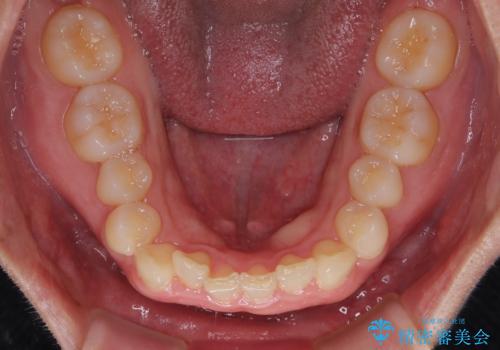

- 下顎前歯が完全に隠れてしまっていることを気にして来院された患者様です。

下顎の臼歯が手前に傾斜していることで咬み合わせが深くなってしまい、下顎前歯が見えないほどに上顎前歯が覆い被さっている状態でした。